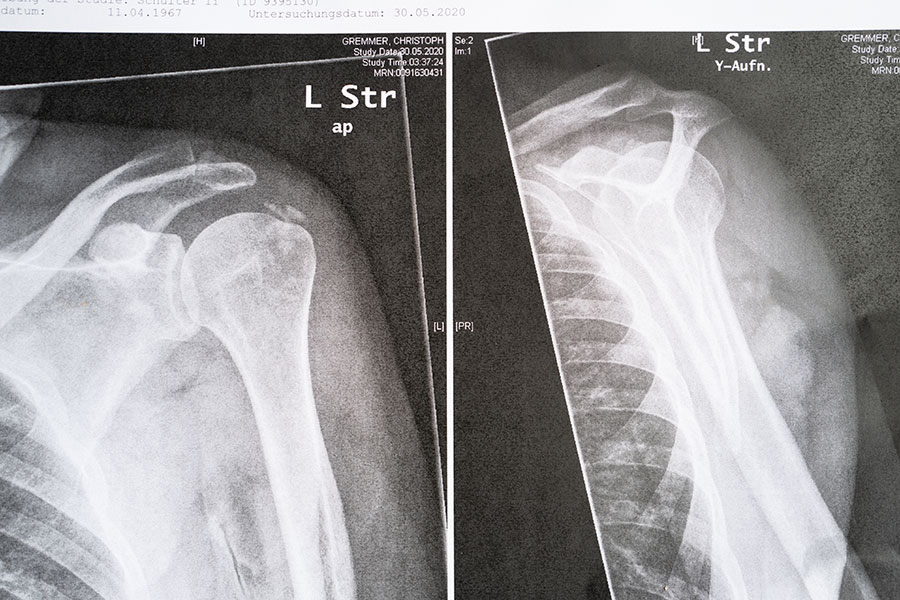

… so ein Bild ist mir immer wieder ein Wunder, dagegen können mir Marienerscheinungen komplett gestohlen bleiben … und wie schön gleichmäßig diese Rippenlinien sind – wie die Spiralfeder vorn in einem Kugelschreiber …